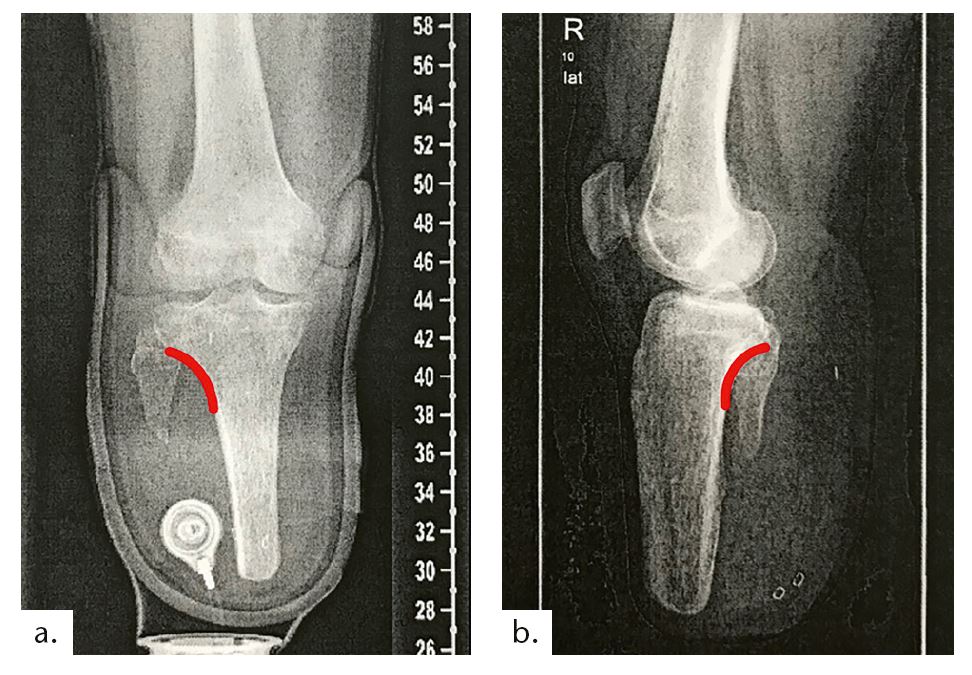

Beim ersten Fallbeispiel handelt es sich um eine 73-jährige Anwenderin (Mobilitätsgrad 2–3), mit einer Körpergröße von 1,53 m und einem Gewicht von 48 kg. Ihre Grunderkrankung besteht in einer Sklerodermie mit daraus resultierender pAVK. Aufgrund dessen wurde im Mai 2014 eine transtibiale Amputation an der linken Seite vorgenommen; eine Revision erfolgte im August 2014. Das Ergebnis ist ein nur 3,5 cm langer Stumpf mit einer Narbenverwachsung am distalen Tibiaende und mit verbliebenem Fibulakopf (Abb. 7 u. 8). An der kontralateralen Seite erfolgte eine Mittelfußamputation (2006); zudem bestehen Einschränkungen der Gelenkbeweglichkeit aller Gelenke mit Greiffunktionsverlust der Hände (Abb. 9). Die besonderen Anforderungen an die Versorgung dieser Patientin ergeben sich aus folgenden Aspekten: